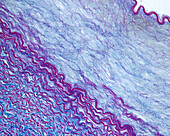

13416586 - Aorta tunica media and adventitia, light micrograph

12634941 - Aorta, tunica adventitia and media, LM

12634940 - Aorta, tunica adventitia and media, LM

12634939 - Aorta, tunica adventitia and media, LM